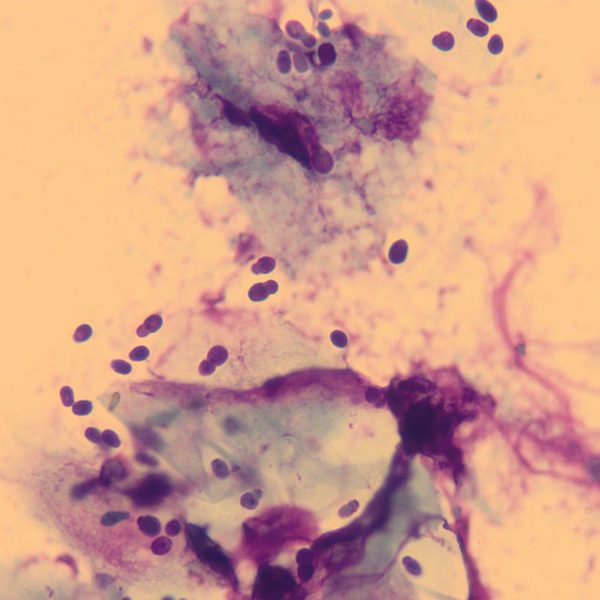

The most useful diagnostic test involves taking a swab or sticky tape sample (tape impression) from the skin for staining and examination under a microscope. This allows examination of the material from the skin surface and assessment of the numbers of microbes on the skin. As Malassezia organisms are present in normal healthy animals, finding low numbers or occasional yeast is not significant. However, in cases of Malassezia dermatitis, yeast can be present in their thousands, and are often associated with inflammatory cells. Malassezia appear as peanut-shaped structures under the microscope and are usually purple/blue in colour due to the staining used for examination (Fig 2).

Fig 2: Peanut-shaped Malassezia yeasts seen through a microscope in a case of Malassezia dermatitis